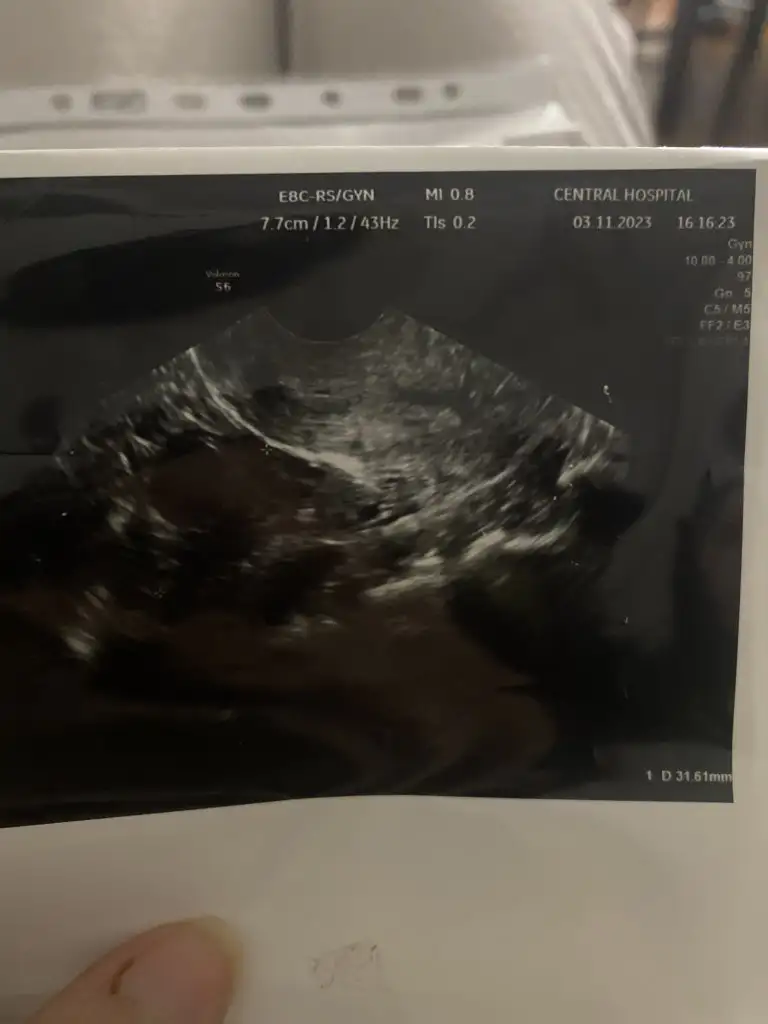

Burada yazmıyor sanırım onu size doktorun söylemesi gerektiArkadaşlar ilaç filan kullanmadım normal kontrol gittim yumurtan gelişmeye başlamış dedi hoca ama ben kaç mm olduğunu sormadım sizce resimde yazanlardan hangisi